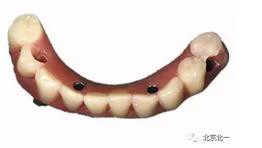

圖七:采用A04技術(shù),拔除下頜余留牙,修整骨平面。在頦孔前方傾斜植入兩枚植體,避開頦孔。減少懸臂。前牙區(qū)植入兩枚直的植體。完成即刻修復(fù)。一日得牙,缺牙后多少年來都沒有吃過蘋果的滋味,到種植牙時(shí)代,想吃什么就吃什么, 我的健康我做主。